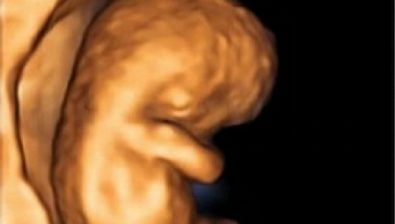

Growing at a rapid pace, your baby is looking determined this week with hands flexed and meeting over the heart area.

The fingers are lengthening and developing touch pads at the ends where fingertips will soon be.

The tadpole-like appearances are diminishing as your baby starts to look more and more human. The neck is straightening out, and there are even tiny eyelids covering almost the entire eye.

With all of this growth and development, your little one has begun to move and kick. Though, you probably won’t feel these tiny movements for a few weeks.